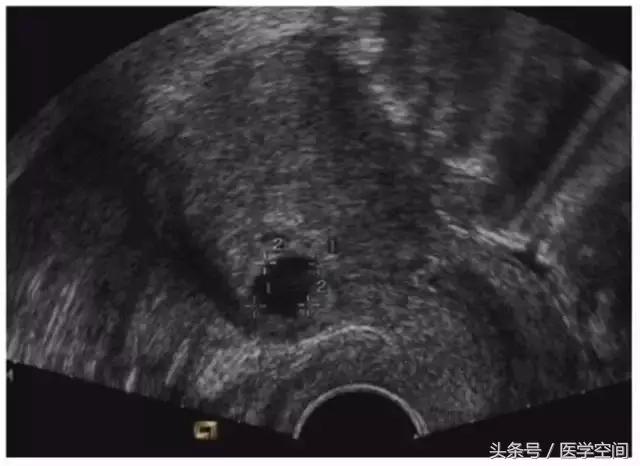

CSP是指妊娠囊着床在前次剖宫产子宫切口的瘢痕处,典型CSP的超声表现主要有:妊娠囊位于前次剖宫产子宫切口处,宫腔内及宫颈管内没有孕囊,邻近膀胱处的子宫肌层变薄(见图1)。呈典型表现的瘢痕妊娠CSP超声诊断很容易。

图1典型CSP的超声表现